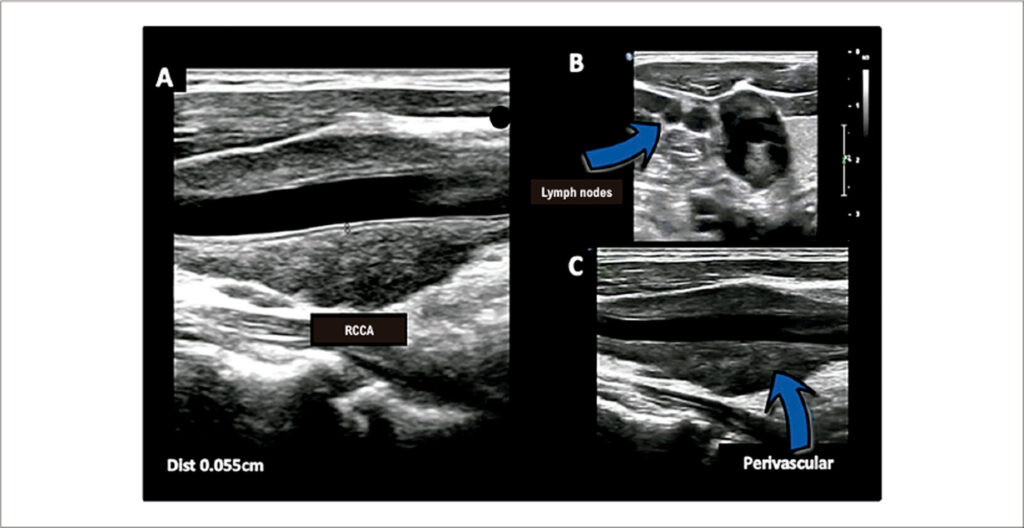

A Rare Case of Pulmonary Sarcoidosis With Extracranial Carotid System Involvement

In sarcoidosis, a noninfectious inflammatory process leads to the formation of granulomas, which predominantly affect the lungs and intrathoracic lymph nodes in approximately 90% to 95% of cases. Close to 30% of patients with sarcoidosis present with extrapulmonary involvement, which may be the primary manifestation of the disease or occur in isolation.–